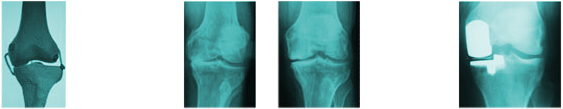

SCORE 3

30%

Medial Wear Bone on Bone

SCORE 4

40%

Medial Wear Bone on Bone Osteophyte Lipping (Lateral)

SCORE 5-1=4

50%

Medial Wear Bone on Bone Osteophyte Lipping (Lateral) AP Subluxation